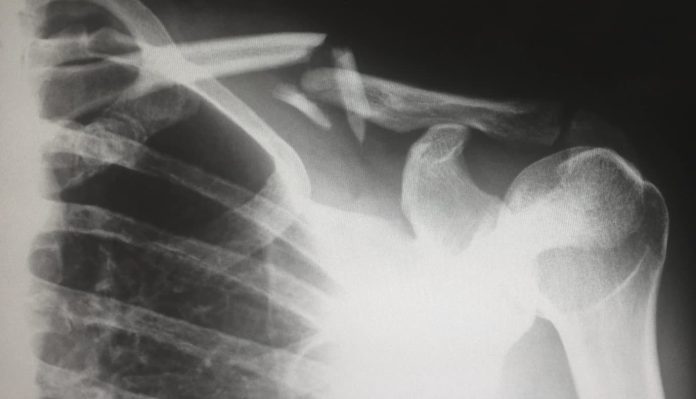

You also need to make sure that whatever your injuries are, they are tended to properly. Your health is, of course, of the utmost importance. After any kind of accident or injury, medical treatment should be the first port of call.

Whether you need the emergency services or simply check yourself into the ER for some treatment, get yourself treated. Your insurance should cover you in the case of an accident, but even if you end up spending money, the hope is that your legal team can help you recover all costs, so don’t worry about expenses at this point.